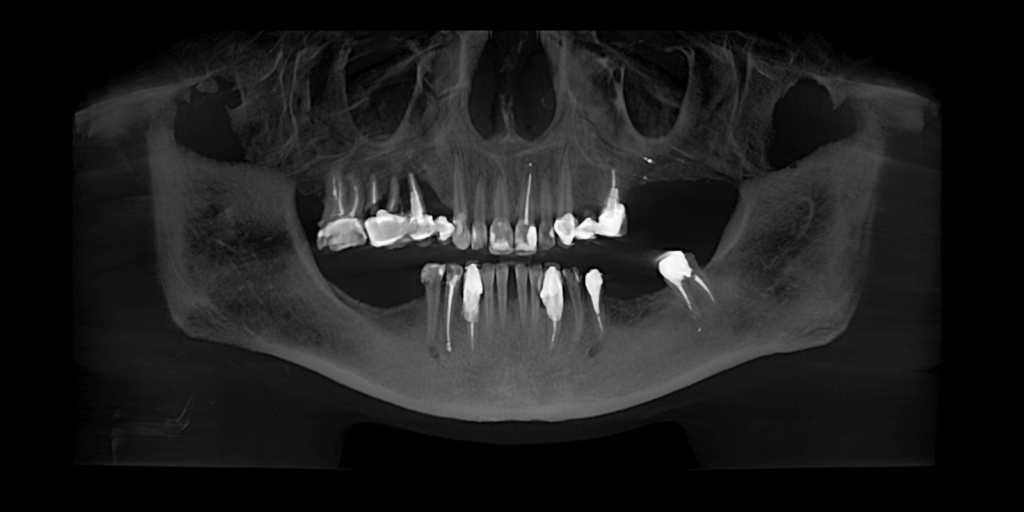

После осмотра врач направил пациентку на 3D КТ-исследование обеих челюстей, чтобы полноценно оценить состояние зубов и предложить обоснованный план лечения. На КТ был выявлен раскол корней зубов под мостовидным протезом на зубах 1.4-1.6.

- Расколотые зубы 1.5, 1.6 (под мостовидным протезом) – удалить.

- Одновременно с удалением выполнить операцию по аугментации костной ткани.

- Отсрочено провести операцию по имплантации в области зубов 1.4 и 1.6.